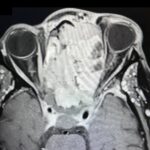

Sinonasal carcinoma is a rare malignancy that often presents with nonspecific symptoms, making early diagnosis challenging. Delayed recognition can lead to disease progression and worse outcomes. This case report emphasizes the importance of early identification, prompt imaging, and multidisciplinary management. A 73-year-old male with a history of anemia and hypertension presented with progressive facial swelling, 20-pound weight loss, and vision loss in the left eye over two months. Initially misdiagnosed with bacterial sinusitis, his symptoms persisted. Examination revealed a proptotic left eye and a large obstructive nasal mass. Computed tomography (CT) and MRI (magnetic resonance imaging) demonstrated a destructive sinonasal mass with skull base and intracranial extension. A biopsy confirmed sinonasal carcinoma, and the patient was started on chemoradiation therapy due to the inoperability of the tumor.

This case underscores the importance of recognizing red flag symptoms such as persistent facial swelling and neurological deficits. Multimodal imaging played a critical role in diagnosis. The literature suggests sinonasal carcinoma is often diagnosed late, reinforcing the need for early suspicion and specialist referral. Sinonasal carcinoma should be considered in patients with persistent facial or nasal symptoms. Timely imaging, biopsy, and interdisciplinary care are essential for optimizing outcomes.